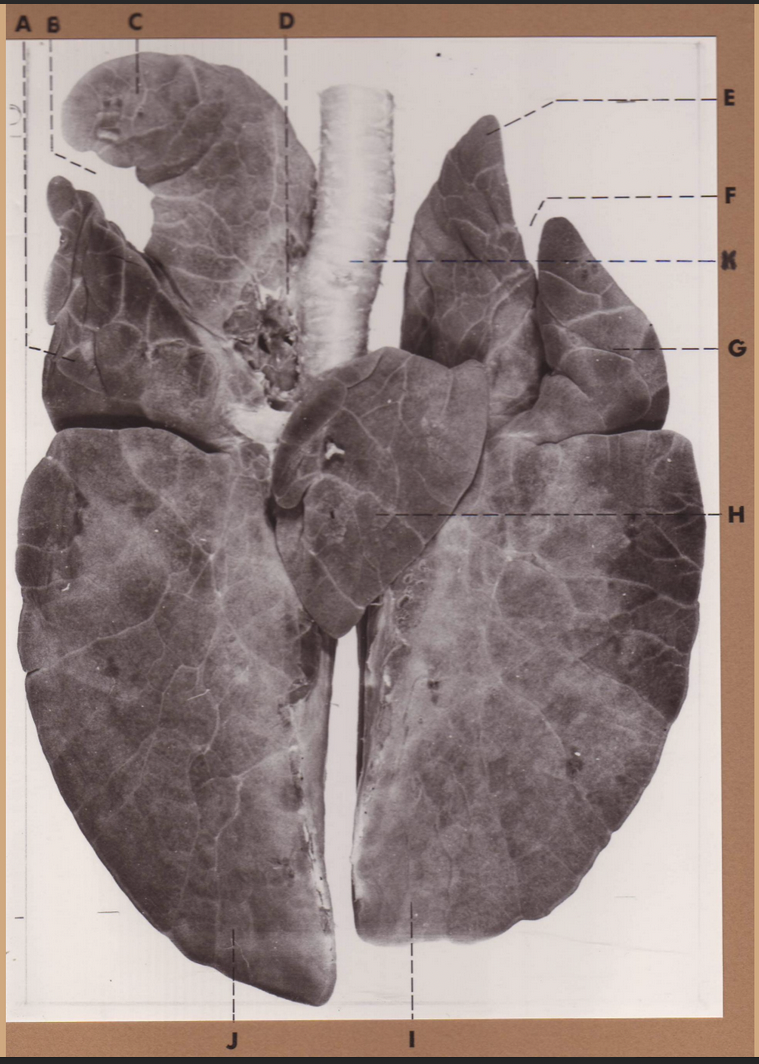

A

(pig lungs, dorsal)

L cranial lobe, caudal segment

B

(pig lungs, dorsal)

L cranial lobe, cranial segment

C

(pig lungs, dorsal)

trachea

D

(pig lungs, dorsal)

R cranial lobe

E

(pig lungs, dorsal)

cardiac notch

F

(pig lungs, dorsal)

middle lobe

G

(pig lungs, dorsal)

dorsal border

H

(pig lungs, dorsal)

costal surface

I

(pig lungs, dorsal)

basal border

J

(pig lungs, dorsal)

R caudal lobe

K

(pig lungs, dorsal)

L caudal lobe